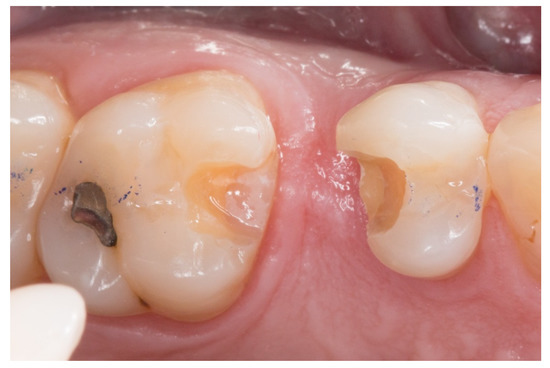

Figure 1.

A posterior maxilla edentulous space.

Figure 2.

The proximal faces of the adjacent teeth delimiting the edentulous space carved up to the level of the ideal point of contact (inlay cavities).

1. The new technique in “T” started once the silicone impressions of the patient were taken for both arches, and an interocclusal registration in the maximal intercuspation position was obtained, in order to prepare (on an articulator) the wax-up and the silicone keys for the tooth replacement [20]. Figure 1 represents the initial state of a case collected in the study.

2. The proximal faces of the adjacent teeth delimiting the edentulous space were carved up to the level of the ideal point of contact (inlay cavities), to position the future horizontal structure of the fiberglass bridge (Figure 2).